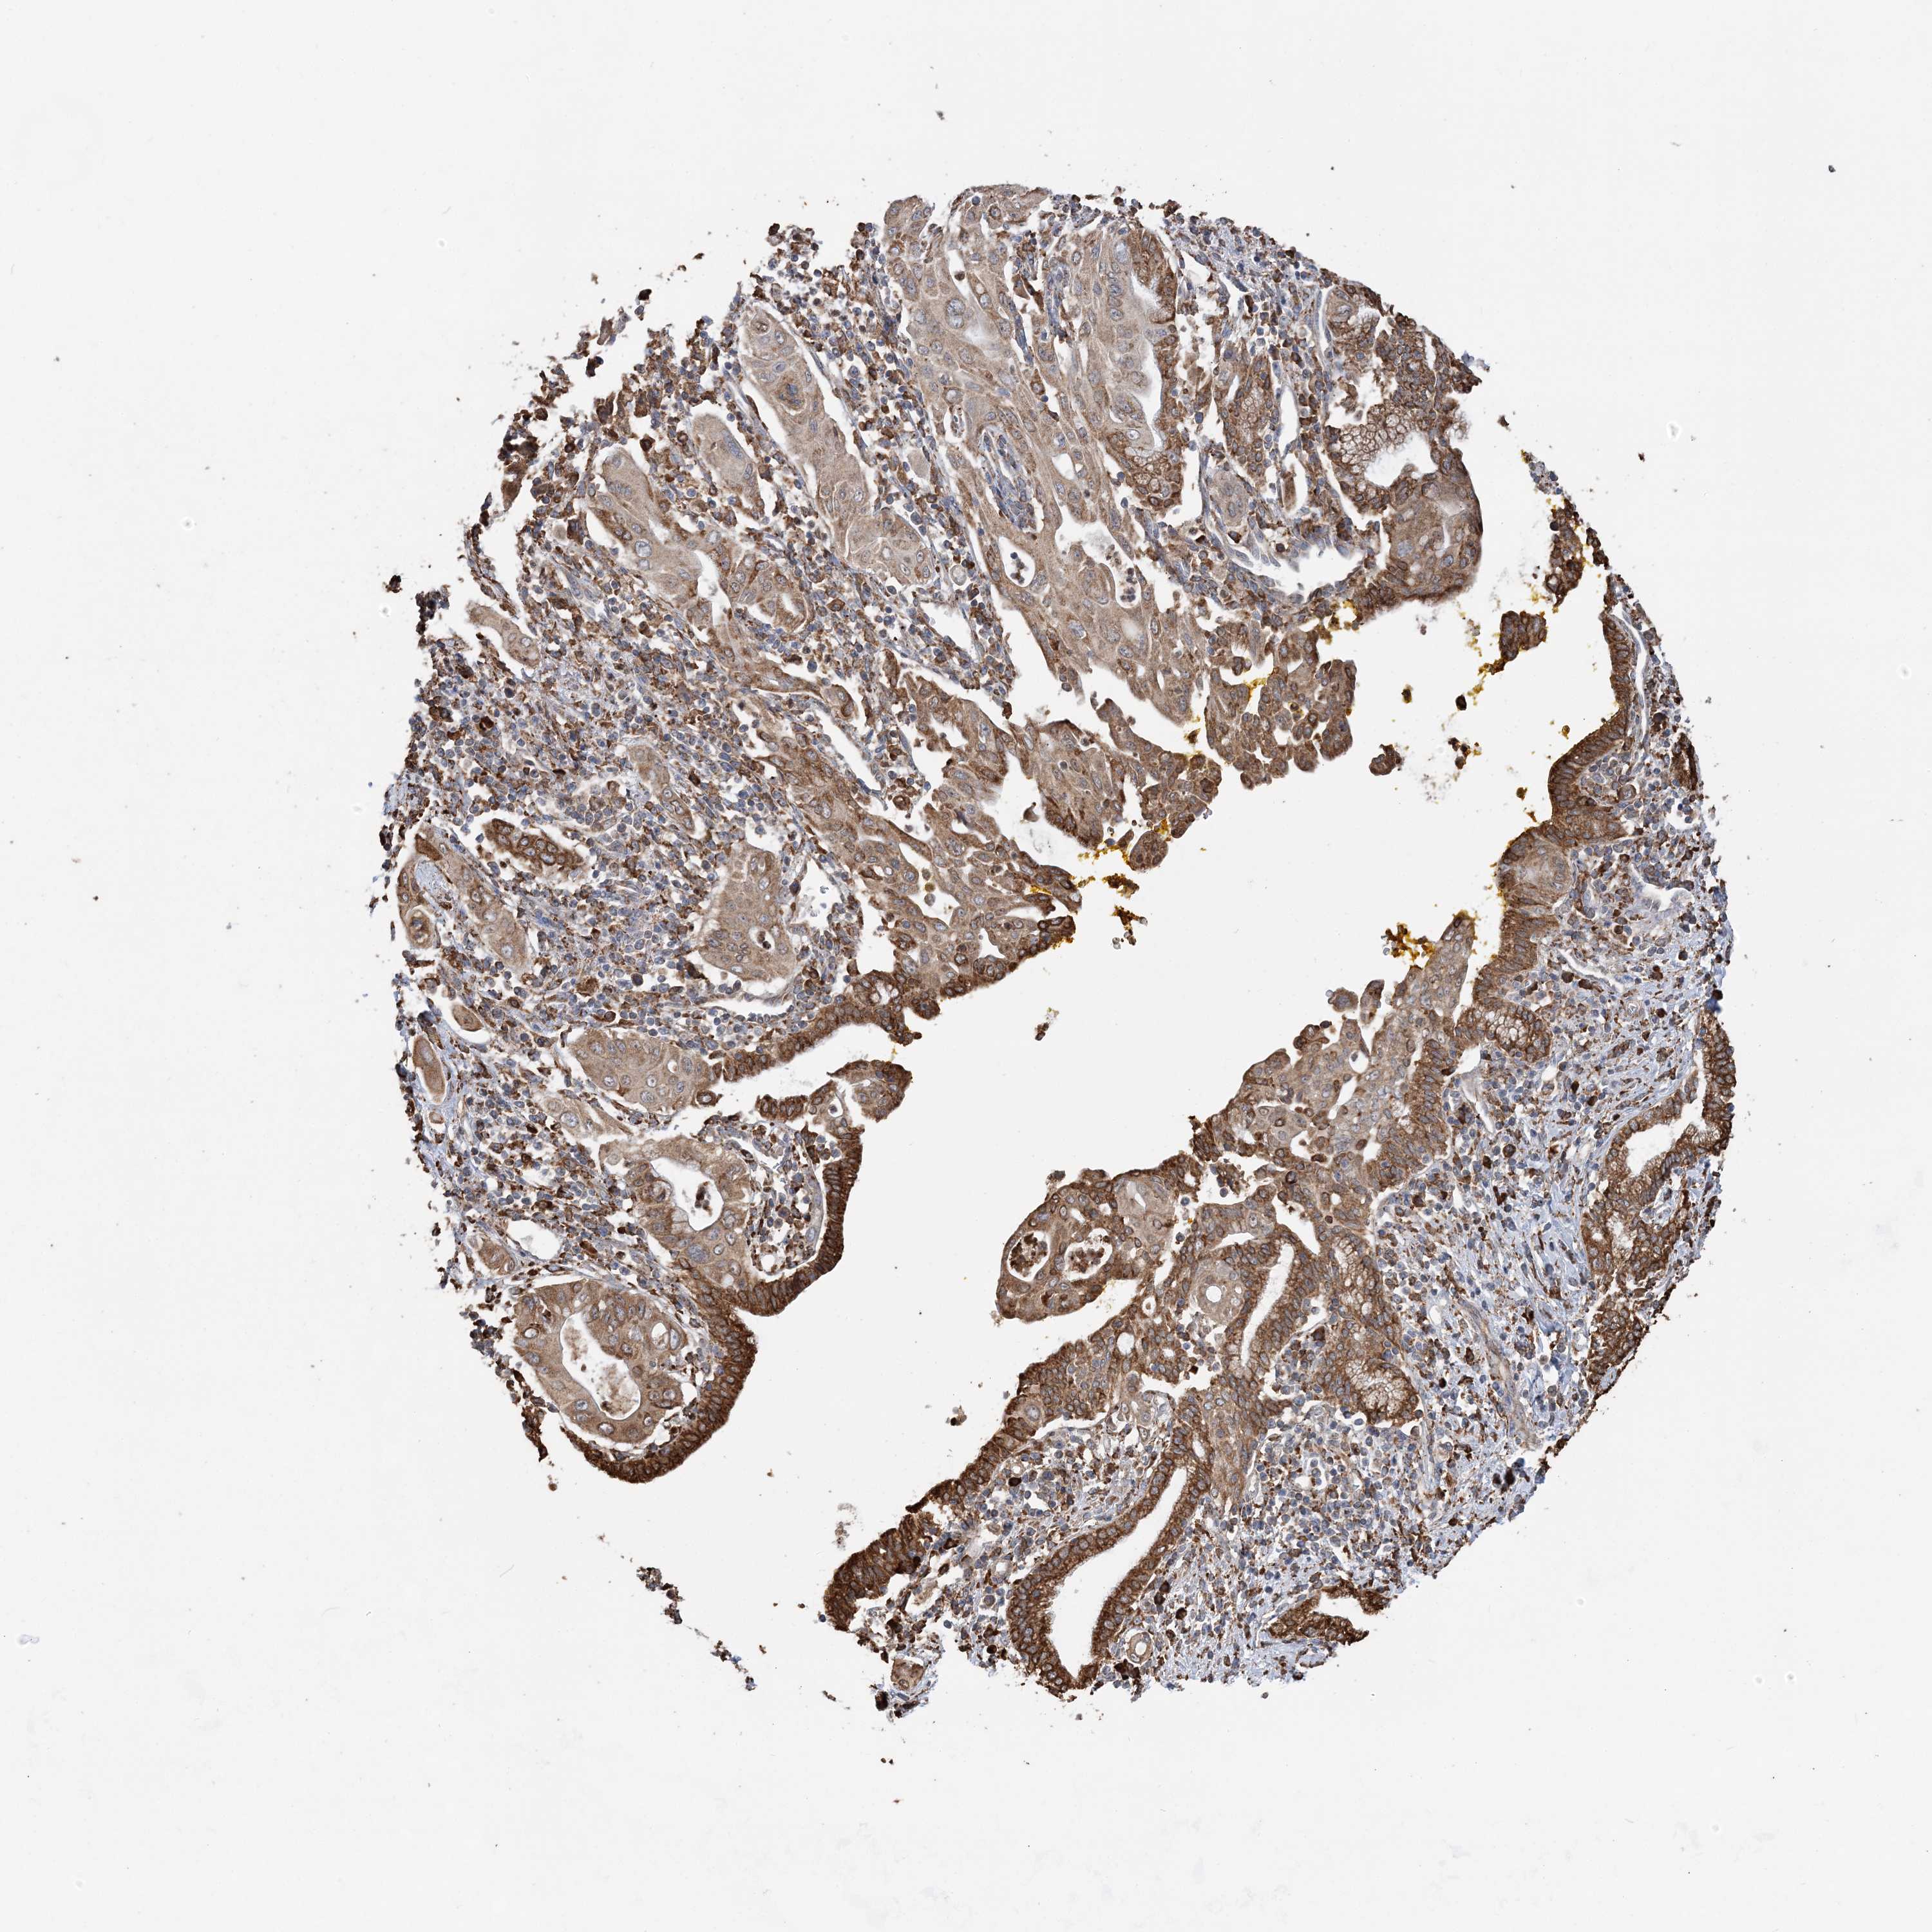

PANCREATIC CANCER - Protein expressioni

A mouse-over function shows sample information and annotation data. Click on an image to view it in a full screen mode. Samples can be filtered based on level of antibody staining by selecting one or several of the following categories: high, medium, low and not detected. The assay and annotation is described here.

Note that samples used for immunohistochemistry by the Human Protein Atlas do not correspond to samples in the TCGA dataset.

Antibody stainingi

Antibody staining in the annotated cell types in the current human tissue is reported as not detected, low, medium, or high, based on conventional immunohistochemistry profiling in selected tissues. This score is based on the combination of the staining intensity and fraction of stained cells.

Each image is clickable and will lead to virtual microscopy that enables deeper exploration of all samples and also displays staining intensity scores, fraction scores and subcellular localization as well as patient and tissue information for each sample.

Antibody HPA036389

Staining

High

Medium

Low

Not detected

Intensity

Strong

Moderate

Weak

Negative

Quantity

>75%

75%-25%

<25%

None

Location

Nuclear

Cytoplasmic/membranous

Cytoplasmic/membranous,nuclear

Adenocarcinoma, NOS